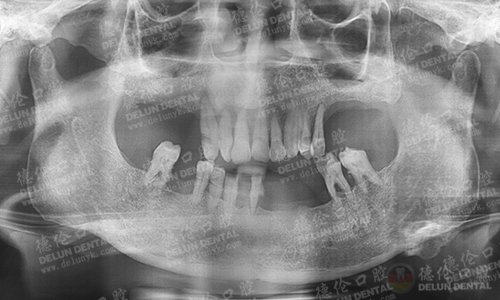

牙齿症状:上排牙缺失8颗,下排牙缺失7颗。

李老伯口腔全景X光片

术前身体、口腔检查

检查完李老伯的口腔情况和身体状况后,德伦口腔的专家团队为他量身定制了一套微创种植牙手术方案,手术过程创口小、出血少、可靠舒适,大大降低患者痛苦程度,适合像李老伯这类害怕疼痛的长者的种牙需求。